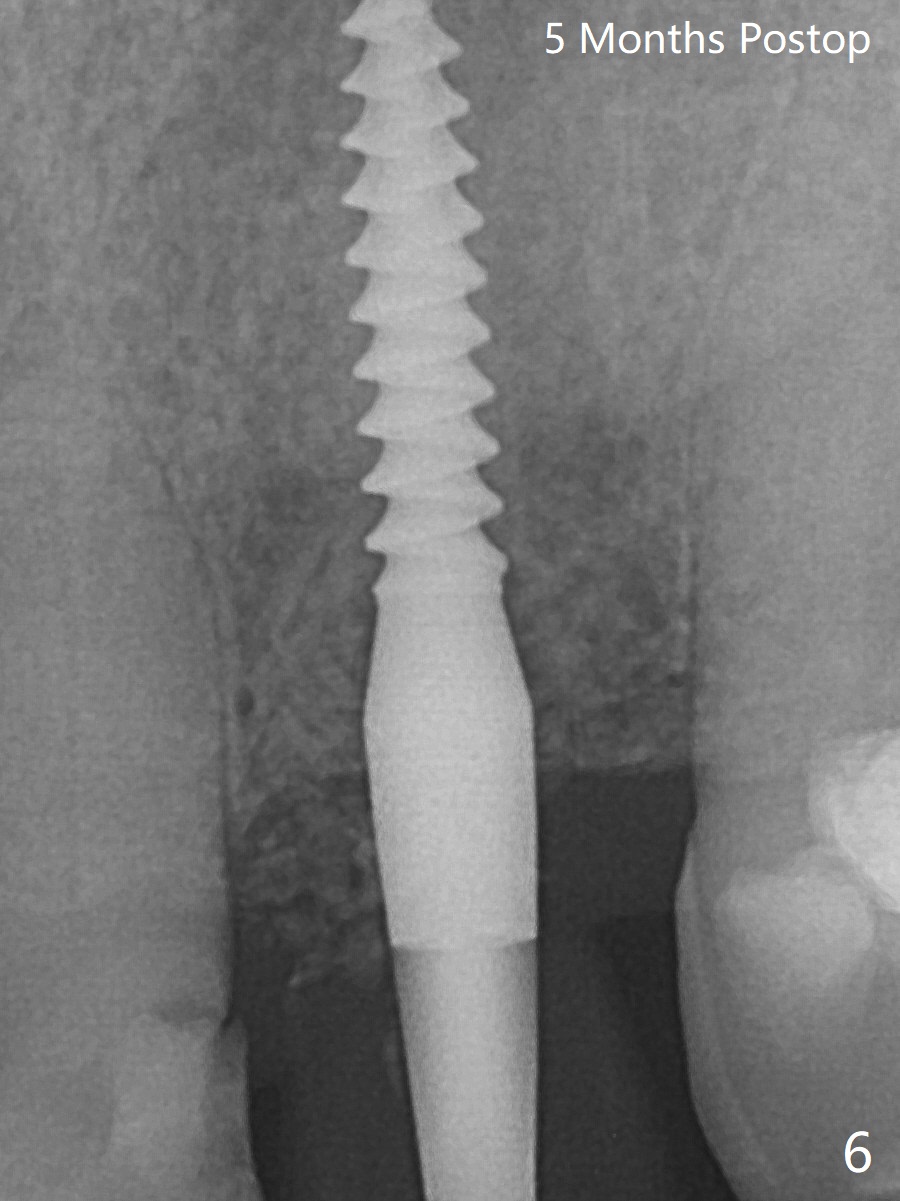

After undersized drilling in depth at #10 (2.2x13 mm (10.5 mm offset), Fig.1), a 2.5x13 mm 1-piece implant is placed with hand driver (Fig.2,3). The implant remains stable 5 months postop (Fig.6). The implant seems to be flexible before heavy occlusal reduction; note the periimplant micro-space (Fig.7). The patient is a bruxer.